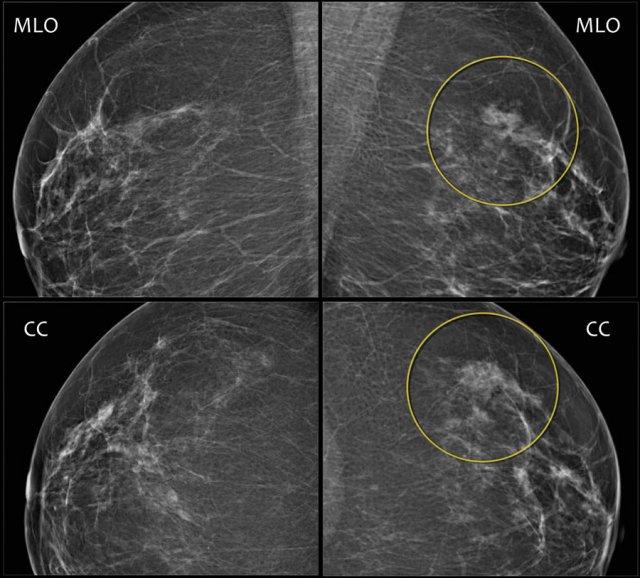

Đây là ví dụ về bất đối xứng khu trú thấy trên tư thế MLO và CC.

Chụp ép khu trú và siêu âm không phát hiện khối nào.